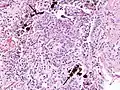

Extensive fibrosis of pleura and lung parenchyma

The arrow points to an uncoated segment of asbestos fiber in this ferruginous body.

Severe pleural fibrosis with focal calcification

The black arrows point to ferrugionous bodies that are located at the periphery of a focus of non-small cell lung carcinoma, NOS.